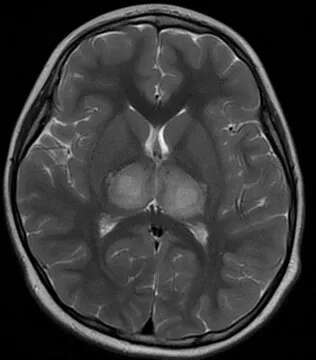

小康入院初时的脑部检查影像图

而小康的头颅MRI检查结果提示

其双侧丘脑、双侧小脑半球

及小脑蚓部异常信号

经综合研判后

考虑是急性坏死性脑病